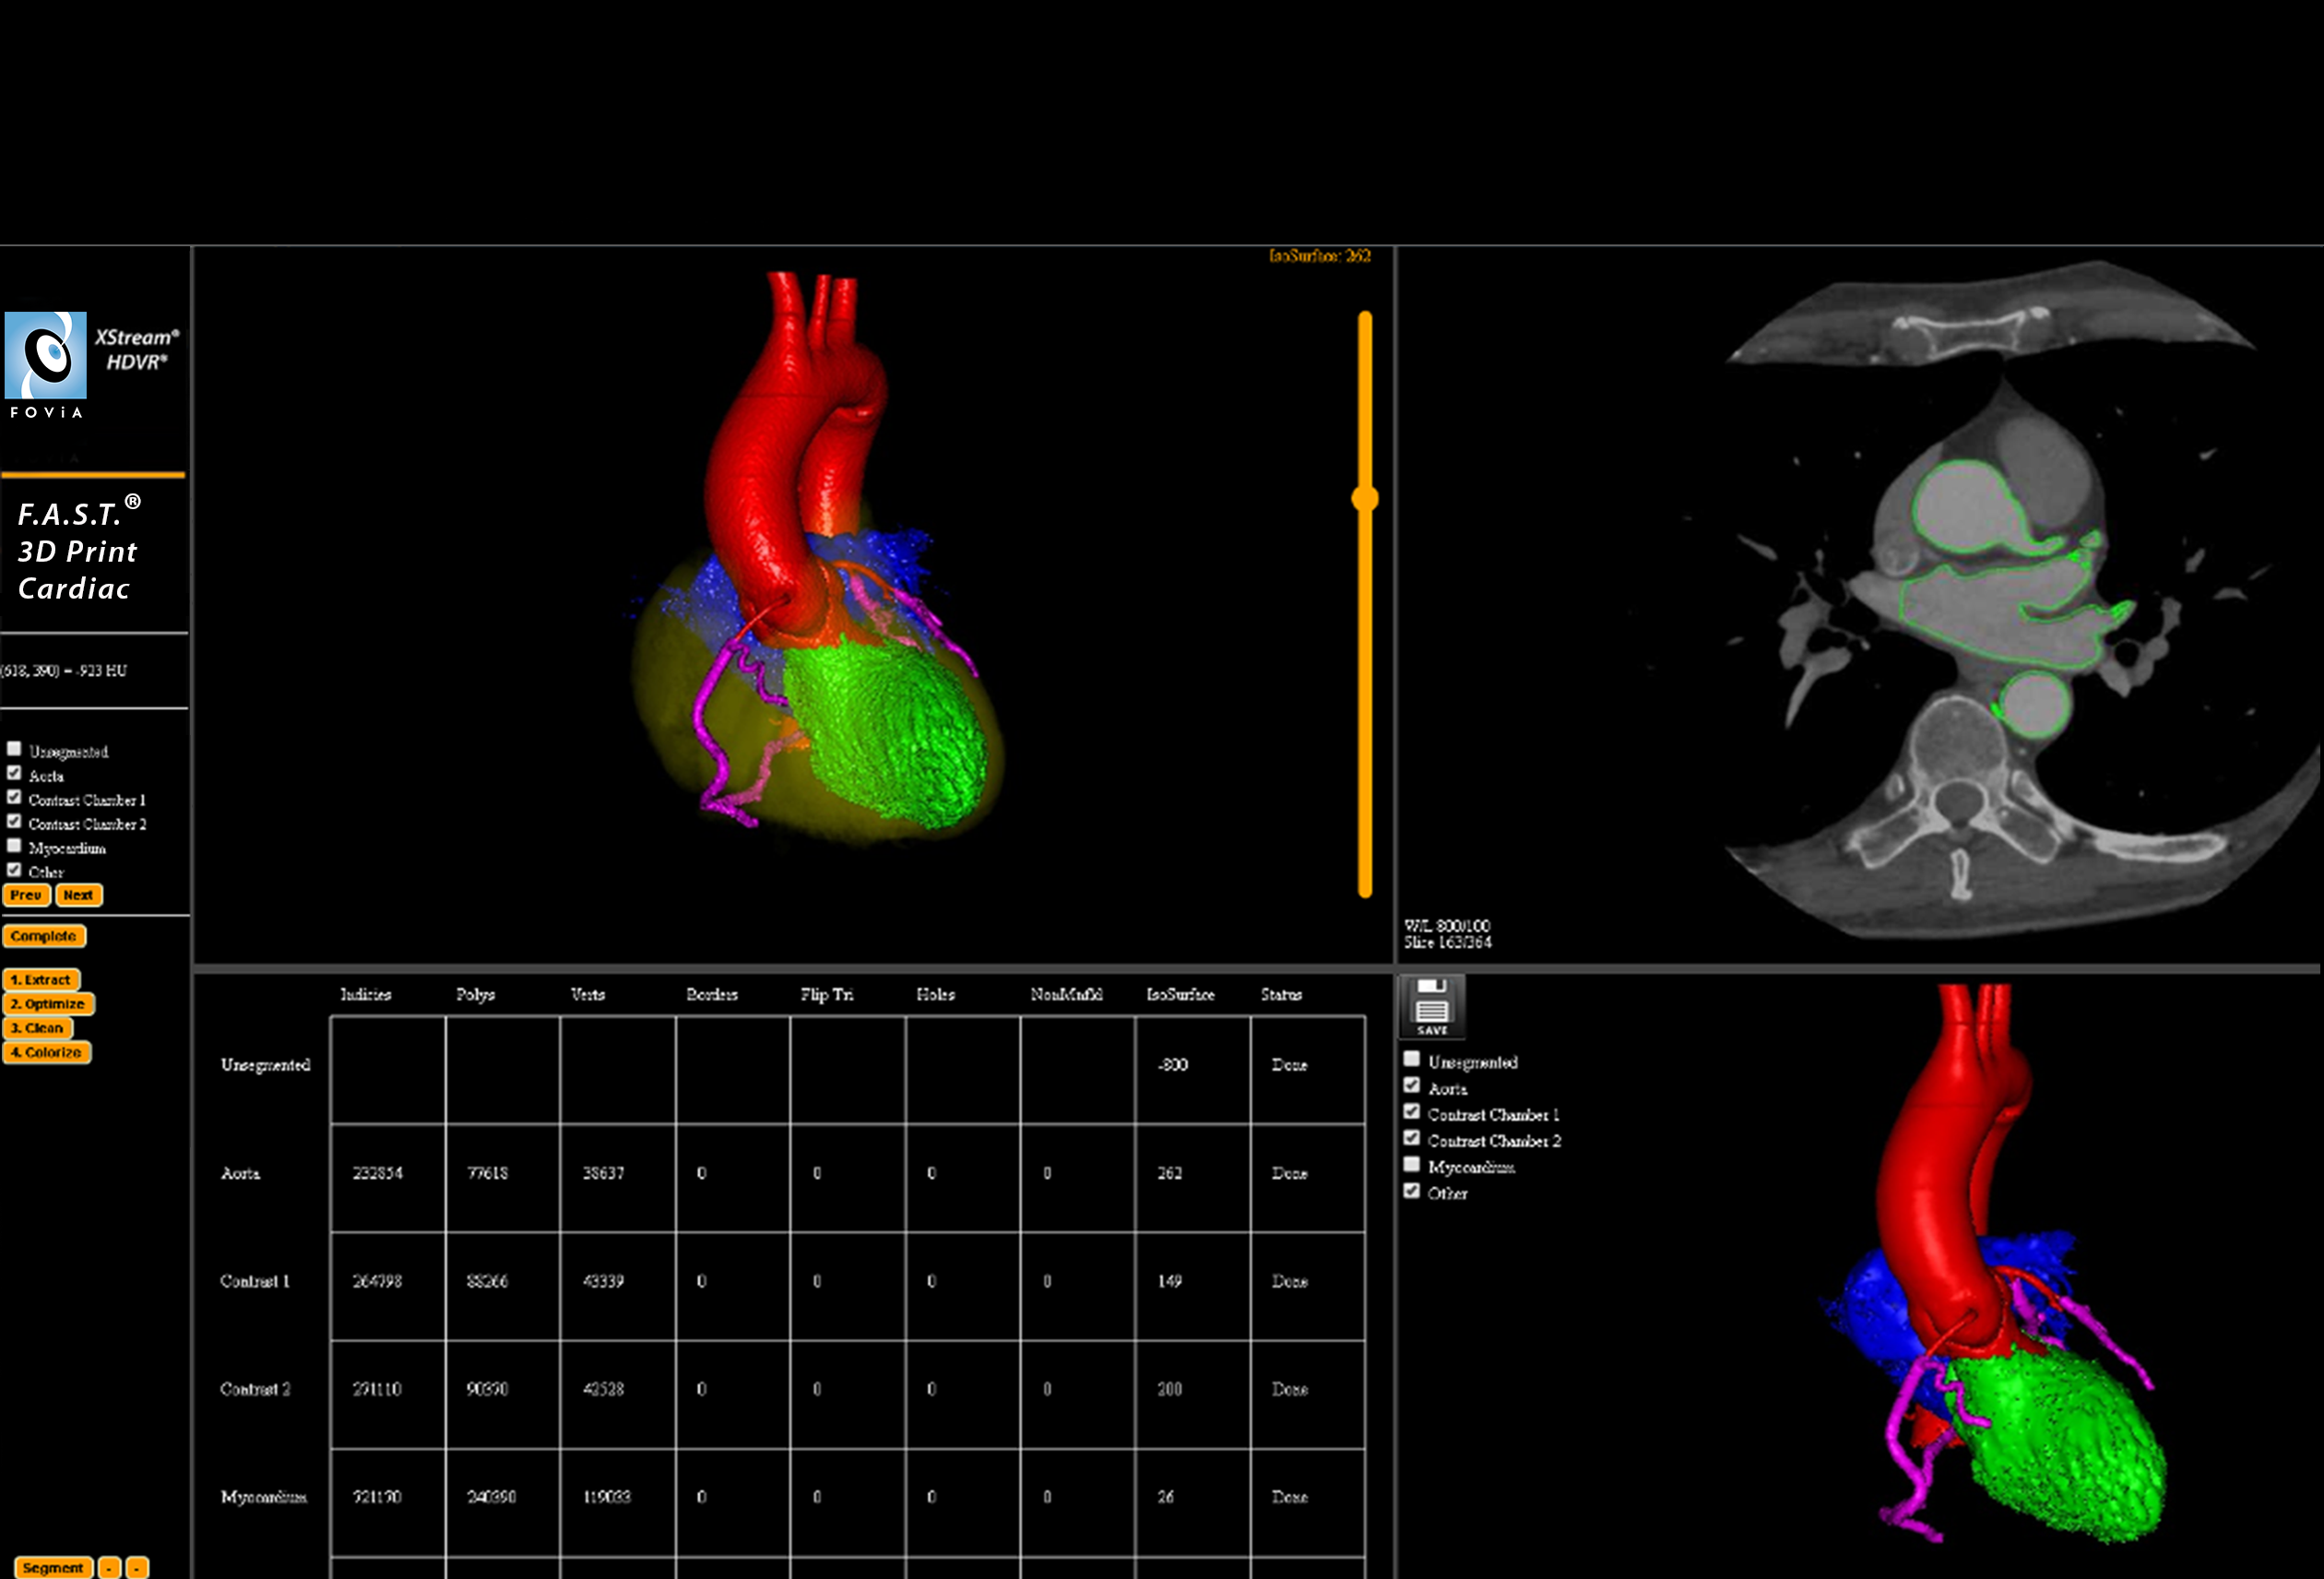

F.A.S.T. 3D Print Cardiac Workflow

F.A.S.T. 3D Print Cardiac Workflow